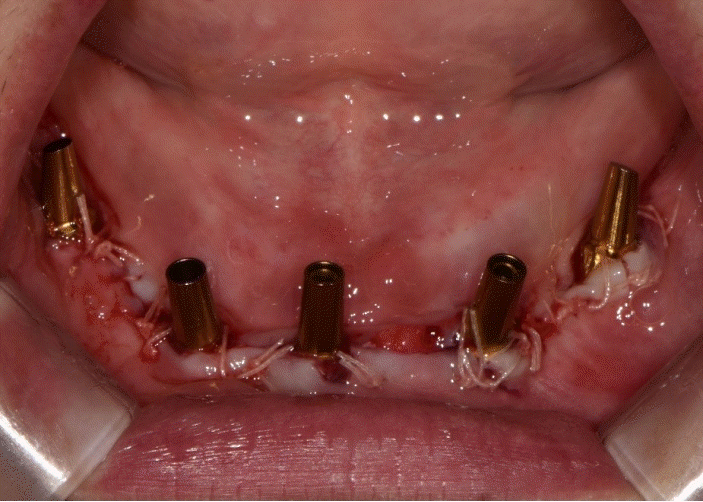

본 증례는 44세 여환으로, 하악 의치가 계속 탈락하여 재제작을 원한다는 주소로 내원하였다. 상악은 고정성 수복물, 그리고 하악은 총의치를 착용 중이었고 하악 양측 구치부의 심한 골 흡수로 인해 유지력 소실로 불편감을 호소하였다. 3개월 전 하악 양측 견치를 발거한 이후로 하악 국소의치를 총의치로 전환하였고, 총의치는 구치부의 심한 교합면 마모와 의치의 후방부가 후구치 삼각 융기를 피개하지 않는 형태였다. 전신 병력으로는 지적장애 및 골관절염으로 약 2개월 간 약물 복용 중이었다. 상악 우측 제1대구치와 제2대구치, 제1소구치 그리고 제2소구치는 우식이 진행된 상태였고, 우측 제2소구치와 우측 제1대구치는 근관치료가 완료된 후 수복되지 않은 상태였다. 상악 좌측 제1소구치와 제2소구치, 그리고 제1대구치 수복물 하방으로 이차 우식이 진행된 상태였고, 전체적으로 교합평면이 균일하지 않은 형태였다(Figs. 1-3).상악 우측 구치부의 수복되지 않은 치아와 상악 좌측 보철물 하방의 이차 우식이 있는 치아는 모두 우식 제거가 필요하여 양측 구치부 각각 3개의 치아는 재수복을 결정하였고, 하악은 구치부의 심한 치조골 흡수로 인해 의치 사용은 불가할 것으로 판단하여 전방부에 임플란트를 식립하여 구치부는 캔틸레버 형태를 가지는 all-on-X 수복을 계획하였다. 의치의 수직고경에 맞춰 교합 평면을 균일하도록 하여 왁스업 시행하였고(Fig. 4), 이후 적절한 교합 수직 고경의 임시 의치를 제작하였다. 약 2개월의 적응기간을 거쳐 의치 적응도와 수직 교합 고경을 평가하였고 적절한 기능과 심미를 확인하였다. 상악 우측 제1소구치와 제2소구치, 제1대구치 그리고 상악 좌측 제1소구치와 제2소구치, 제1대구치는 우식을 제거한 다음, 임시 보철물로 재수복하여 적절한 교합 평면을 설정하였다(Fig. 5).환자가 적응한 임시 의치를 모델 스캔(Medit T710, Medit, Seoul, Korea)하여 프린팅용 레진(Graphy Tera Harz SG-100, Graphy, Seoul, Korea)을 이용하여 3D 프린팅하였고, 출력된 의치에 방사선 불투과성 레진(G-æenial Universal Flo, GC, Luzern, Swiss)을 부착하여 레진 마커를 형성하였다. 레진 마커를 부착한 프린팅 의치를 장착한 채로 콘빔 전산화 단층촬영(CBCT, R2 Studio Q, Megagen, Seoul, Korea)를 촬영하였다(Fig. 6). 촬영한 CBCT 데이터와 의치 스캔 파일을 중첩하여 CAD 소프트웨어(R2 Studio Q, Megagen, Seoul)를 통해 이상적인 임플란트 식립을 계획하였다. 전후방 거리를 연장하여 적절한 캔틸레버를 부여하기 위해 전방부에 3개의 임플란트를 식립하고, 양측 후방부에는 약 30도 경사진 임플란트를 식립하도록 계획하였다(Fig. 7).가이드는 상악의 자연 치열과 대합되는 의치 복제 형태의 상부 가이드, 그리고 가이드 핀이 존재하는 하부 가이드로 이루어지도록 디자인되었다(Fig. 8). 상부 가이드는 임시 의치의 스캔 데이터를 이용해 상부 가이드의 하부면과 하부 가이드의 상부면이 장착되어 구내에서 적합될 수 있도록 CAD 소프트웨어(Meshmixer, Autodesk, San Francisco, CA, USA) 상에서 디자인되었다. 임시 의치의 하부면과 하부가이드의 하부면을 치은과 중첩시켜 어버트먼트의 위치에 홀을 형성한 다음 3D 프린팅(Graphy Tera Harz SG-100, Graphy, Seoul, Korea) 하였다. 수술 당일 장착될 임시 보철물 또한 동일한 CAD 소프트웨어를 통해 제작하였다.수술 당일 이중 가이드를 구내에 장착하여 하부가이드를 고정 핀으로 고정시킨 후(Fig. 9), 계획된 위치에 임플란트 고정체를 식립하였다. 임플란트는 5개 모두 외부 연결형 고정체(AnyOne External, Megagen, Seoul, Korea)를 사용하였고, 식립 시 식립 토크는 모두 40N 이상, ISQ는 70이상으로 양호한 초기 고정력을 확보하였다(Fig. 10). 즉시 부하를 위해 기성 어버트먼트를 체결하였고, 임시 보철물을 장착하여 양측 소구치부에서의 균일한 교합을 확인하였다(Fig. 11).임플란트 주위 골과 치은의 회복을 위해 약 2달간 임시 보철물을 경과 관찰하였고, 이후 최종 보철을 위한 인상 채득을 시행하였다. 상하악 임시 보철물을 장착한 중심교합 상태에서 구내 스캔(Trios 4, 3 Shape, Copenhagen, Denmark)을 시행하여 악간 관계를 채득하였다(Fig. 12). 임시 보철물을 제거한 상태에서 하악의 전방부 3개의 임플란트에 scan body(Scan Abutment, Megagen, Seoul, Korea)를 연결하고, 양측 최후방 임플란트 2개에는 각각 Ti base multi-unit abutment(multi-angled abutment, Osstem, Seoul, South of Korea)를 30Ncm으로 체결한 후 multi scan body(TS Multi scanbody, Osstem, Seoul, Korea)를 연결하여 구내 스캔(Trios 4, 3Shape, Copenhagen, Denmark)을 시행하였다. 이후 스캔 바디를 연결하여 채득한 스캔 파일을 상하악 임시 보철물 상태에서 채득한 스캔 파일과 중첩하여 CAD 소프트웨어(exocad GmbH, Darmstadt, Germany)에서 최종 보철물을 디자인하였다(Fig. 13).최종 보철물은 양측 최후방 임플란트 고정체에 각각 Ti-base(TS multi Ti base, Osstem, Seoul, Korea)와 접착된 나사 유지형 단일 지르코니아 크라운으로, 지르코니아 블록(Zircen, Kuwotech, Gwangju, Korea)을 밀링하여 제작하였고, 치경부 하방으로 포세린으로 치은 형태를 부여하였다. 전방부 3개의 임플란트 고정체에는 맞춤형 지대주를 제작하여 30N으로 체결하였고, 양측 최후방 고정체는 20Ncm으로 체결한 후 레진 시멘트(Rely X U200; 3M ESPE, St. Paul, MN, USA)로 접착 시행하였다. 장착 후 중심교합시 양측의 제1대구치 부위에서 교합력이 적게 가해지도록 교합 조정 시행하였으며, 전방과 측방운동시에 임플란트 상호보호교합이 되도록 조정하였다. 또한 연결부 하방으로 치실을 통과시켜 치은 점막 사이 공간을 평가하였으며, 구강 위생 관리의 용이성을 확인하였다. 이후 1주, 1개월, 3개월 경과 관찰하였고, 환자는 저작이나 심미, 발음 등에서 만족해하였다(Figs. 14 and 15).

Fig. 8.

A. Under part of surgical guide with fixation pin is situated on dental stone cast. B. Upper part of surgical guide is overlapped with under part.